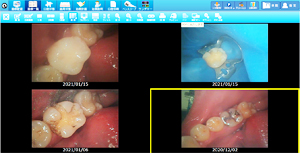

• ラバーダムを使用した治療画像